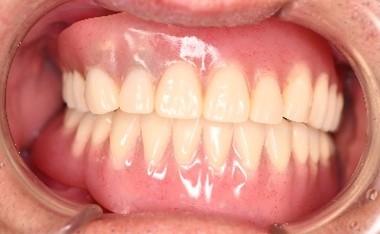

Before

After

【義歯を装着したところ】

【義歯を外したところ】

治療内容

歯周病が重度に進行していました。保存することができない2本の歯を抜歯しました。歯周病の治療を徹底的にし、保存可能な9本の歯の根管治療をし、それらの歯を活用しマグネット式総入れ歯を入れました。

所感

通常の部分入れ歯にすると、入れ歯の支台になる歯は、早期に失われる可能性が高かったです。マグネット式総入れ歯は、支台になる歯に側方への力がかからないため、歯周病が進み歯の周りの骨が少なくなっている歯も効果的に活用できますし、かつ残っている歯を長持ちさせることができます。残っている歯が少なくなってきて、入れ歯で対応する場合は、マグネット式総義歯はとても良い治療法だと考えます。下顎の歯もすべて治療希望で、現在治療中です。下顎については、治療完了後に、あらためてご報告いたします。